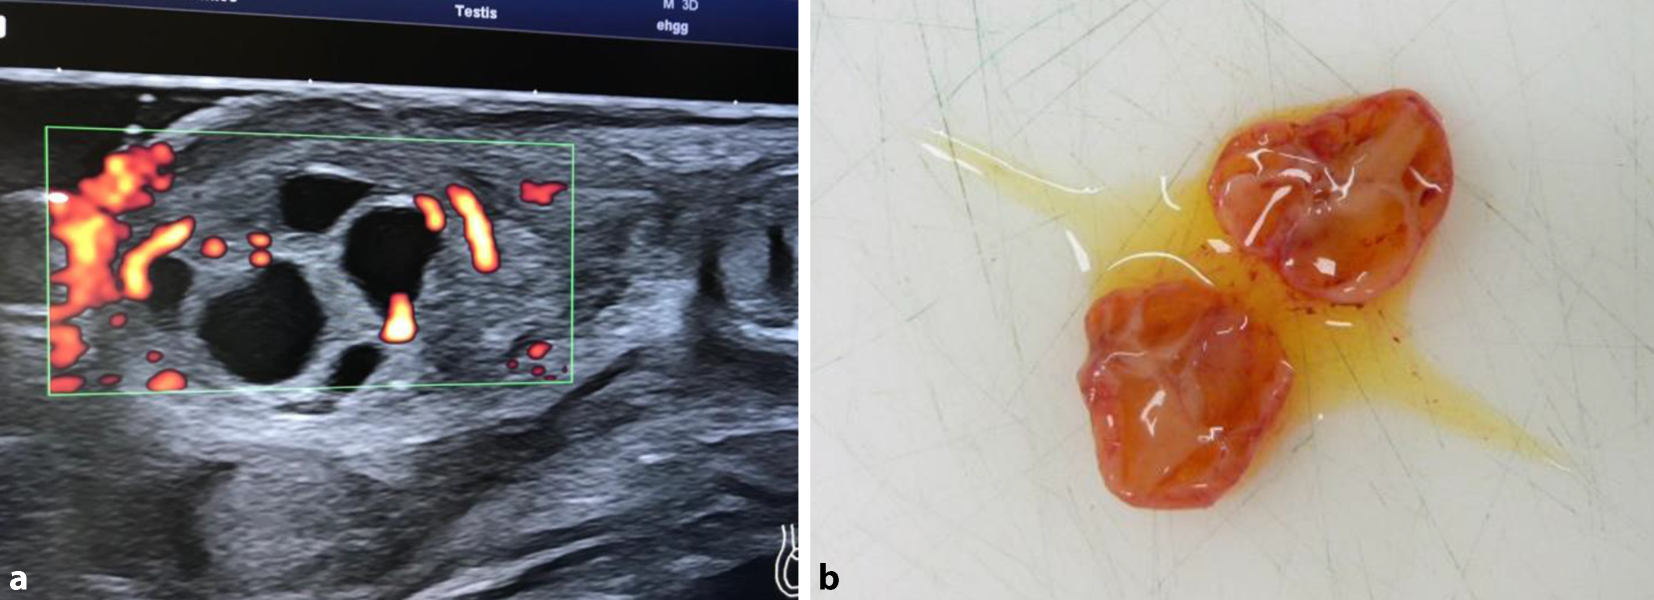

Ein Junge wird reif (39 + 2 SSW) mit Geburtsgewicht von 3530 g geboren. Im Rahmen der U2 fällt ein vergrößertes linkes Hemiskrotum mit palpatorisch verhärtetem Hoden auf. In der Sonographie (Abb. 2a) zeigen sich multiple zystische Veränderungen des Hodenparenchyms, die Abdomensonographie ist unauffällig. AFP 48.370 ng/ml, β‑HCG 0,3 U/l, LDH 428 U/l. Zu diesem Zeitpunkt wird der Verdacht auf einen JGZT gestellt. Am fünften Lebenstag erfolgt die inguinale Freilegung mit Tumorenukleation und Hodenerhalt links. Die Verdachtsdiagnose wird histologisch und später referenzpathologisch bestätigt. Entlassung am Folgetag. Vier Monate postoperativ zeigt sich ein klinisch und sonographisch unauffälliger Befund.

Abb. 2

Fall C: a Hodensonogramm (Power-Doppler), b makropathologischer Befund (b mit freundl. Genehmigung durch Dr. Esther Hanspeter und Dr. Domenico Damiani, Bozen, all rights reserved)